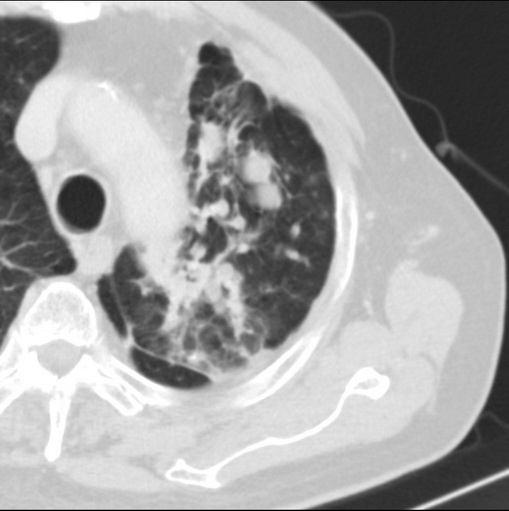

标题: CT25434:胸部CT增强扫描

男性患者 81岁 咳嗽 咳痰 咯血

强化较典型,左上肺癌并纵膈淋巴结转移;左上肺结核并空洞形成;胸膜增厚.

变态反应性支气管肺曲霉菌病与鳞癌鉴别,前者可能性大,左侧胸膜肥厚。

肿块贴近左肺门,包绕左上肺动脉,形态不规则。肿块增强扫描中度强化。纵膈内主动脉弓左旁间隙、气管隆突前、下间隙见多枚淋巴结影。综上考虑左侧中央型肺癌可能性大。图片没有完整上传,尤其是左肺上叶支气管分支层面没有上传,因此不好判断是叶支气管中断还是段支气管中断。另外,下图红色部分所示是“黏液支气管征”吗?